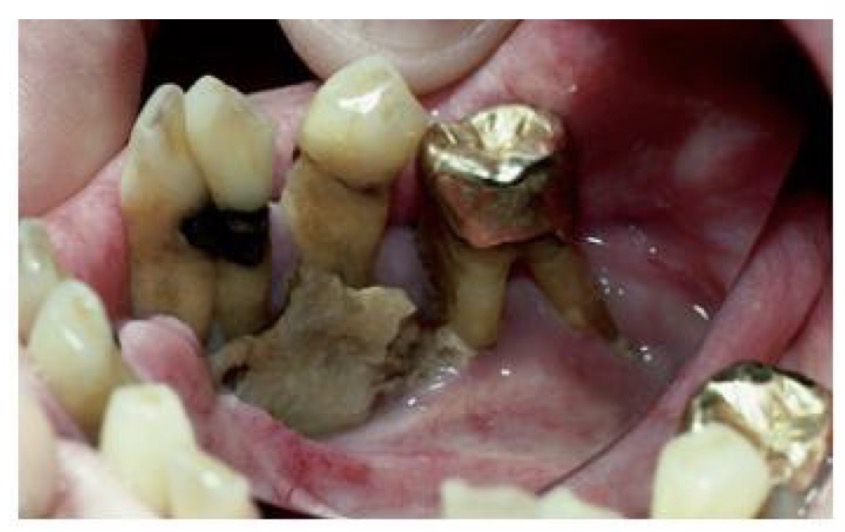

CHẨN ĐOÁN ?

SÂU RĂNG SAU XẠ TRỊ( sâu nhiều răng và lang quanh cổ răng)